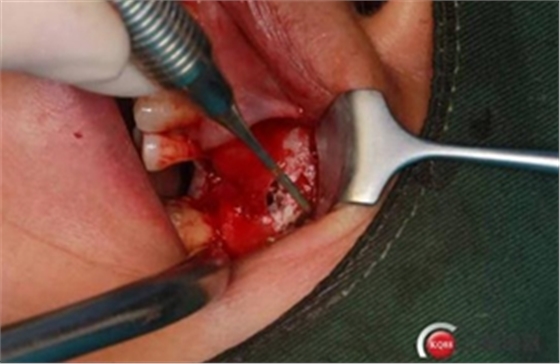

大家好,我是梁老師的助理小依。由于梁老師每天手術(shù)檔期安排較滿,加上經(jīng)常出差講課,沒有時間整理病例 。為了方便大家更及時的了解梁老師最新手術(shù)動態(tài),以后將由我為大家整理并推送梁老師最新經(jīng)典案例。案例文字旁白少,但圖片會盡量完整展示手術(shù)全過程,供大家學(xué)習(xí)參考。有任何問題,可以留言,梁老師會親自為大家解答。感謝大家對梁老師的支持和關(guān)注!